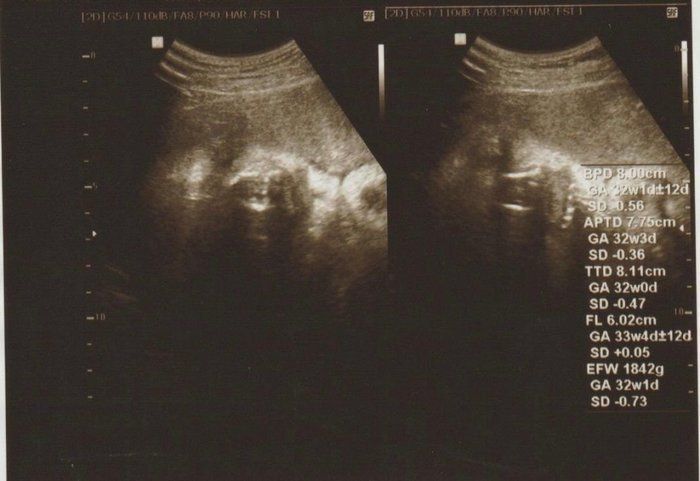

こぢんまり子さんの妊娠33週目のエコー写真 転院することに

エコー写真は、ちょっとわかりにくいですが右側が頭、左側がお尻です。少しくびれたところが首、真ん中上下に腕が伸びています。左側、お尻の上下に足が見えます。赤ちゃんの推定体重は1735g。標準値を下回ってしまいました。何らかの原因で赤ちゃんの育ちが悪いと診断され、大きな病院への転院が決まります。とても動揺して、ネットで赤ちゃんの育ちが悪い原因を調べるなど、不安が消えない日々を過ごしました。

家から徒歩5分の産院から、車で1時間ほどの大学病院に転院することになりました。3ヶ所の大きな病院から選ぶように言われ、なんとなく車で行きやすそうなところに決めました。結婚で引っ越してきた土地なので、病院の情報や土地勘がありません。今思えば、一度持ち帰って、きちんと検討すればよかったと少し後悔しています。